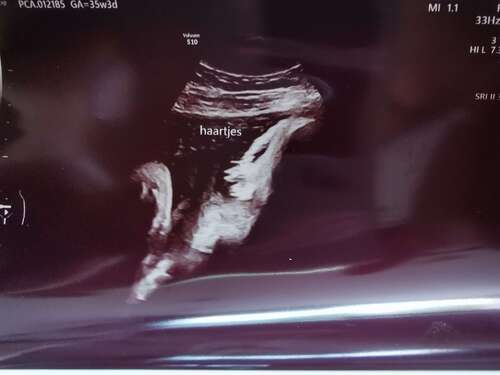

Hier ook haartjes van 3 cm lang gezien op de groei echo met 35 weken .. ben benieuwd straks 😊